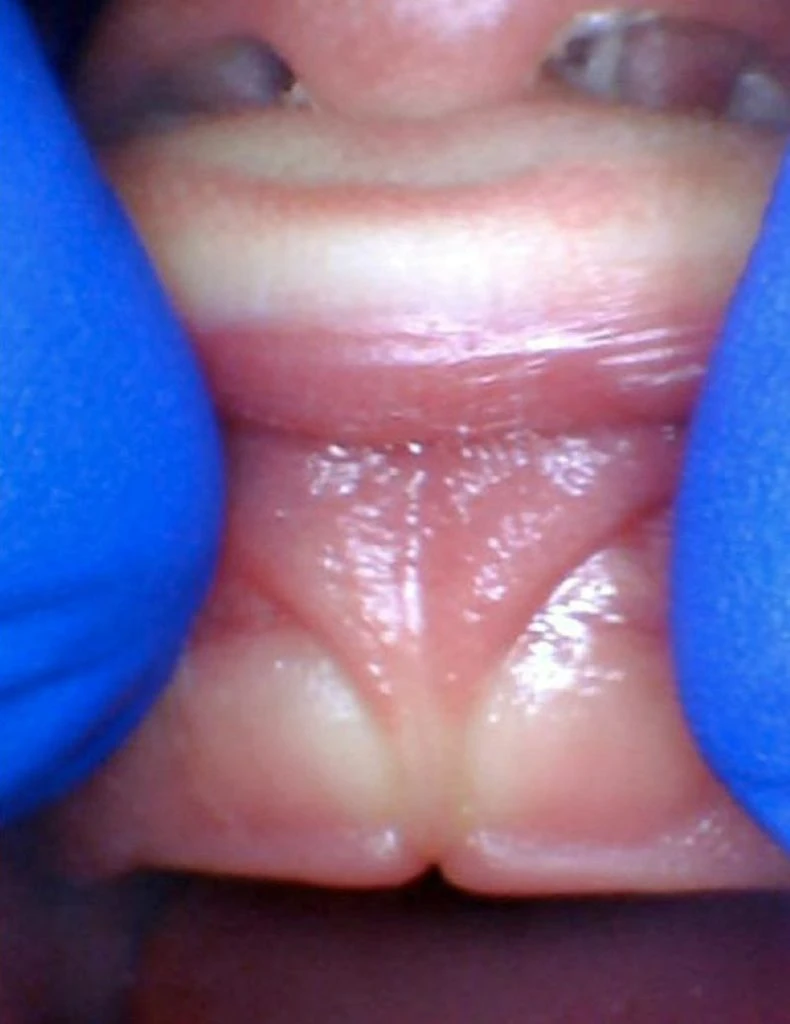

These images show the spectrum of lip restriction in an infant.

View lip restrictions